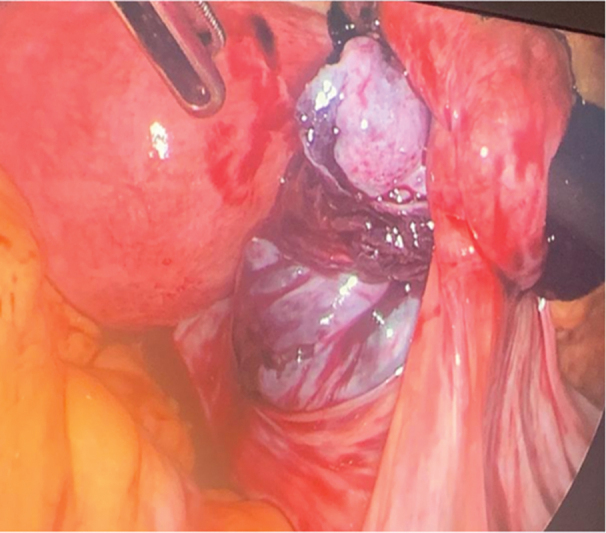

卵巢扭转是妇科急症之一,手术治疗是挽救卵巢的标准方法,同时也能发现一些意外的解剖缺陷,这些缺陷会增加卵巢扭转的风险。我们报告了一例因怀疑卵巢扭转而接受腹腔镜诊断的 27 岁单身女性病例。术中,我们发现右侧附件扭转(卵巢和输卵管),右侧卵巢和输卵管嵌顿在位于右侧子宫骶骨韧带内侧的大腹膜囊中。使用非创伤性腹腔镜镊子将肿胀的附件剥离并小心拉至大腹膜囊外侧。左侧附件正常。患者进行了第二次腹腔镜检查,计划对大腹膜缺损进行腹膜闭合。以前曾有两例报告过卵巢嵌顿,但与卵巢扭转无关,也不涉及腹膜闭合,与我们报告的卵巢剥离和腹膜缺损闭合不同。这种情况的病因可能是先天性的,因为没有其他明显的病因,如盆腔创伤、既往手术、盆腔炎或子宫内膜异位症。我们的临床评估表明,腹膜囊可以防止卵巢自发剥离,从而加强卵巢扭转的进程,使其在被困在腹膜囊中时发生缺血性病变。这种情况会导致囊壁之间的细胞受压,随后组织水肿,从而增强缺血效应。

Ovarian torsion is one of the gynecological emergencies and surgical intervention is the standard management for ovarian salvage as well as reveals some unexpected anatomical defects that increase the risk of ovarian torsion. We report a case of a 27-year-old single, nulliparous female taken for diagnostic laparoscopy with suspicion of ovarian torsion. Intraoperatively, we found right adnexa torsion (ovary with tube) along with incarceration of the right ovary and tube into the big peritoneal sac, which was located medial to the right uterosacral ligament. Detorsion and careful pulling of the swollen adnexa were done to the outside of the big peritoneal sac using nontraumatic laparoscopic forceps. The left side was normal with normal left adnexa. The patient had a second laparoscopic look with a plan for peritoneal closure of the big peritoneal defect. There are two cases which have previously reported ovarian incarceration, but were not associated with ovarian torsion, and did not involve peritoneal closure unlike our report of ovarian detorsion and peritoneal defect closure. The etiology of this condition is thought to be likely congenital as there were no other visible etiologies like pelvic trauma, previous surgery, pelvic inflammatory disease, or endometriosis. Our clinical assessment suggests that a peritoneal sac can enhance the course of ovarian torsion to involve ischemic changes of the ovary when trapped inside of it, by its prevention of spontaneous detorsion. This condition will result in the compression of the cells between the sac wall and subsequent tissue edema enhancing the ischemic effect.